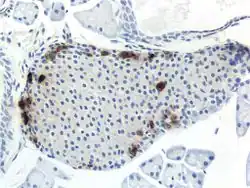

Additional images